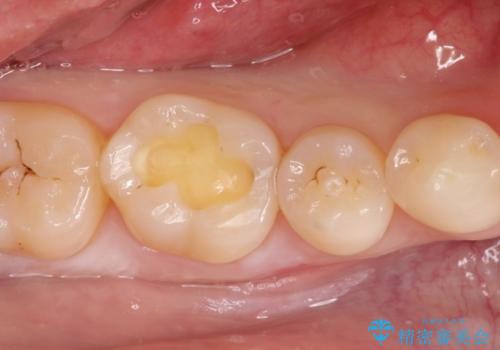

メタルフリーの治療 セラミックインレー

- メタルインレーによる審美障害を主訴に来院されました。

セラミックインレーに治療を行っております。

e-max プレスインレーにて修復治療を行っているため適合性及び審美性の高い治療を行うことができます